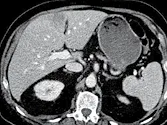

Figure 3. Métastases hépatiques d’un cancer du colon.

A. Examen initial montrant que le grand axe de la lésion est de 81 mm.

B. Après quatre cycles de chimiothérapie, la lésion mesure 59 mm, soit une amélioration de 27 %. Bien que la lésion ait visuellement diminué de façon évidente, il ne s’agit pas encore d’une réponse partielle, car le cap des 30 %

de diminution n’est pas franchi. La réponse est classée « SD »